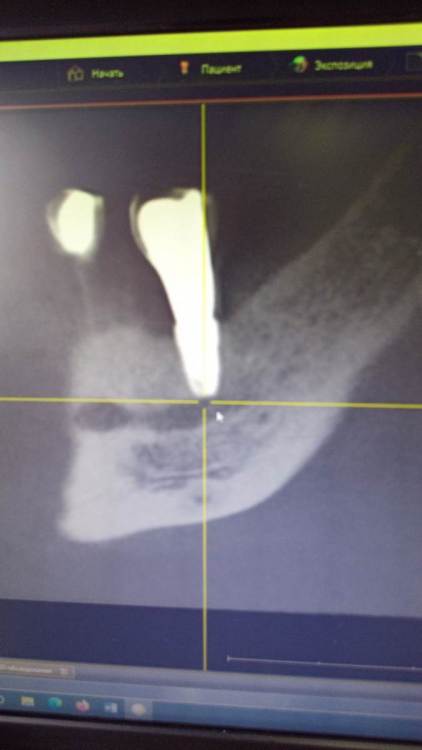

Зндрю Опубликовано 2 февраля, 2024 Автор Поделиться Опубликовано 2 февраля, 2024 (изменено) КТ имеется . Окончание импланта лежит на нижней ветви тройничного нерва, но не травмирует его. Со слов независимого имплантолога, у которого был на консультации, иначе симптомы были бы неврологические , а их нет . Изменено 2 февраля, 2024 пользователем Зндрю Ссылка на комментарий

kramer Опубликовано 7 февраля, 2024 Поделиться Опубликовано 7 февраля, 2024 В принципе понятно. Лично мое мнение, что надо удалять оба имплантата (ближний выглядит недозаглубоенным (плохо видно), дальний слишком близко к нерву, что скорее всего и дает симптомы. Установить новые импланты, сделать мостовидную конструкцию. Ссылка на комментарий

Зндрю Опубликовано 7 февраля, 2024 Автор Поделиться Опубликовано 7 февраля, 2024 (изменено) 3 часа назад, kramer сказал: В принципе понятно. Лично мое мнение, что надо удалять оба имплантата (ближний выглядит недозаглубоенным (плохо видно), дальний слишком близко к нерву, что скорее всего и дает симптомы. Установить новые импланты, сделать мостовидную конструкцию. На месте дальнего годом раньше стоял аналогичный имплант, но он был расположен выше. Период интеграции с костью сроком в 4 месяца он пережил успешно, а вот после установки формирователя десны началось воспаление, сопровождаемое обильной грануляцией десны, которое закончилось периимплантитом и удалением данного импланта . Через полгода на это же место был установлен нынешний имплант, но уже с максимальным погружением в кость. При его установке врач попал мне им в тройниный нерв, это было ясно потому как меня словно током ударило. Он тут же открутил его немного обратно и спросил меня, чувствую ли я боль, на что я ответил что нет . Он так и оставил, и дальнейший период интеграции с костью проходил без осложнений. Установка формирователя десны тоже осложнений не вызвала , боли начались только после установки коронки. Самое главное - что первый винт стоял на достаточном расстоянии от нижней ветви тройничного нерва, но болевые ощущения была абсолютно идентичны что и со вторым винтом - а именно появлялись исключительно через несколько часов после вкручивания коронки, при этом я даже еще ни разу не успевал ничего жевать . Изменено 7 февраля, 2024 пользователем Зндрю Ссылка на комментарий